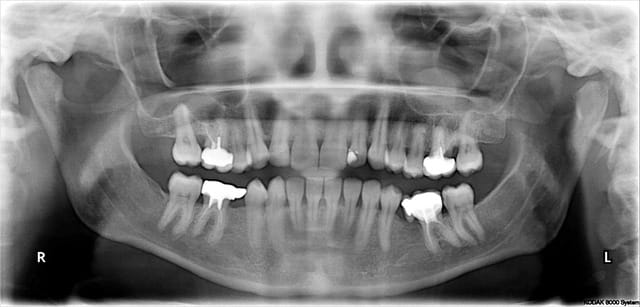

nouvelle patiente 32 ans, sous méthotrexate IV depuis 1 à 2 ans pour polyarthrite, première consult pour changer des vieilles couronnes.

Comment interpretez-vous l'image au niveau du sinus gauche ? Sa régularité m'inquiète... ;-)

c'est un polype il me semble

Pseudokyste muqueux ou alors un mucocele

Faire un scan mais surveillance dans le premier cas qui est le plus probable.

Le côté régulier est plutôt rassurant pour moi en général.

la boule dans le sinus n'est pas de ton ressort mais la lésion en regard sur la 6, elle l'est

oui oui en effet, y'a du taf de tous les cotés !